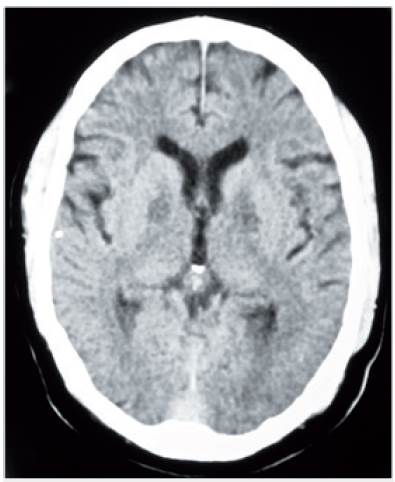

Se le dio manejo de sostén y el 23/9/13 fue valorado por neurología, que lo encuentra soñoliento, con signos vitales normales, lenguaje escaso fluente, moderada confusión mental y sin alteraciones focales. El cuadro hemático, la química sanguínea que incluyó las pruebas de función hepática y el parcial de orina fueron normales. Se le realizaron gases arteriales que fueron normales y se le solicitó estudio de medición de metanol, el cual no se pudo realizar. Se le solicitó una resonancia magnética (RM) de cerebro simple (26/9/13) que mostró lesiones bilaterales simétricas hipointensas en T1 e hiperintensas en FLAIR, T2 y DWI de los globos pálidos, de los hipocampos y de la corteza cerebral paramediana frontal (figura 2).

Resonancia magnética de cerebro simple: (a) lesiones hiperintensas de los globos pálidos en la secuencia axial del FLAIR; (b) corte coronal en T2, lesiones hiperintensas con centro hipointenso de los globos pálidos, lesiones homogéneamente hiperintensas de los hipocampos; (c) corte axial en DWI que muestra restricción de la difusión en los globos pálidos y en la corteza cerebral frontal paramediana bilateral; (d) y (e) cortes axiales en DWI que muestran restricción de la difusión en los hipocampos.

Figura 2: Resonancia magnética de cerebro simple: (a) lesiones hiperintensas de los globos pálidos en la secuencia axial del FLAIR; (b) corte coronal en T2, lesiones hiperintensas con centro hipointenso de los globos pálidos, lesiones homogéneamente hiperintensas de los hipocampos; (c) corte axial en DWI que muestra restricción de la difusión en los globos pálidos y en la corteza cerebral frontal paramediana bilateral; (d) y (e) cortes axiales en DWI que muestran restricción de la difusión en los hipocampos.

Fuente: autores.